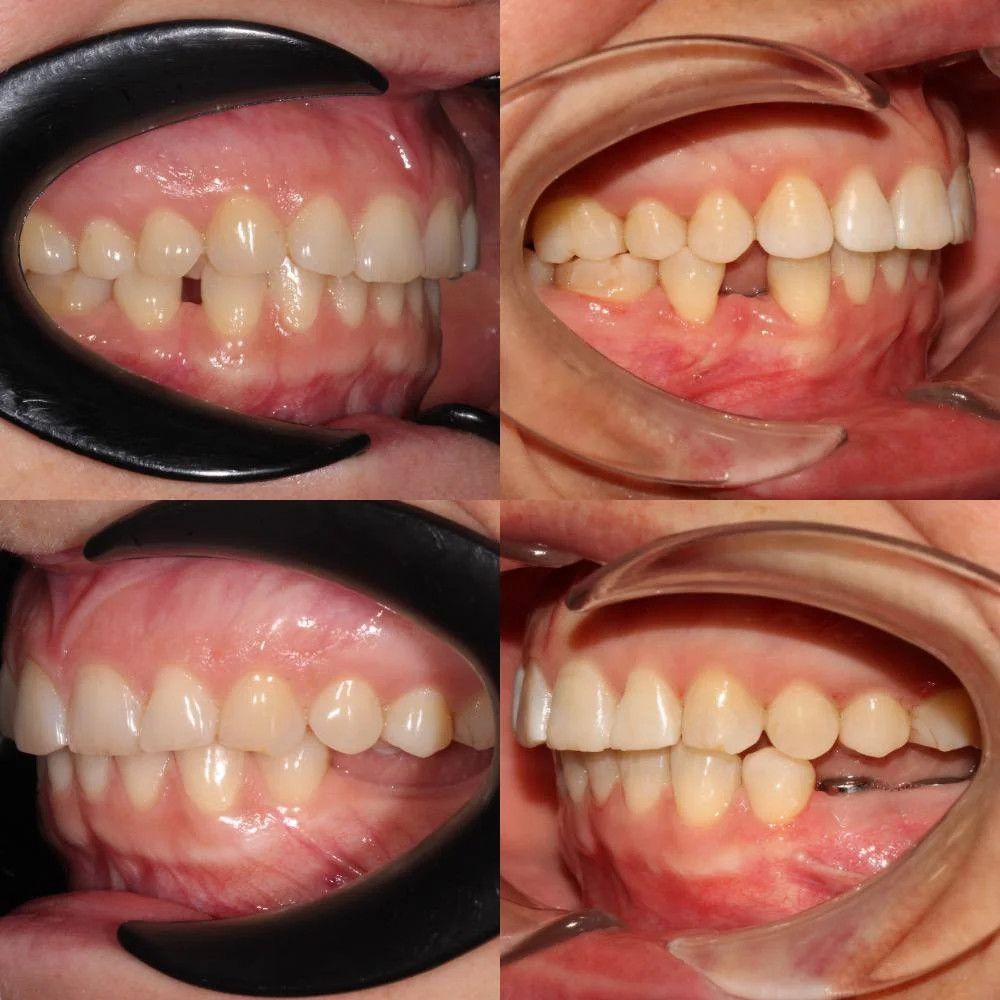

Ход лечения

Лечение заняло 28 месяцев (ноябрь 2023 — март 2026). После снятия брекетов пациентка направлена к ортопеду для установки коронок.

Решение: Установили металлические самолигирующие брекеты H4 на обе челюсти. За 28 месяцев выровняли зубы и привели прикус в норму. После снятия брекетов зафиксировали ретейнеры на обе челюсти. Пациентка направлена к ортопеду — в течение недели устанавливает коронки, после чего будет проведено сканирование и изготовлены ретенционные капы уже по окончательному контуру зубов.